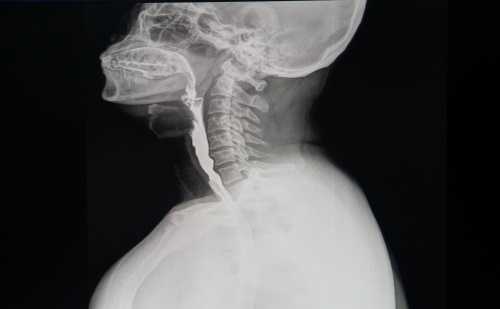

Рентгенограмма, КТ при папилломе пищевода